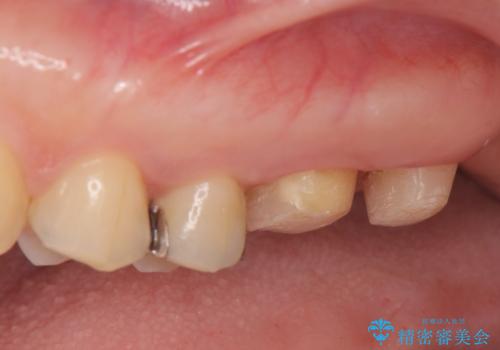

- 銀歯をやりかえたいが他院で抜歯と言われセカンドオピニオンで来院。適合の悪い被せ物が入っており、まずは古い材料、虫歯をとり保存可能か確かめる必要があり、拡大鏡下で全て取り除いたら歯質が歯茎の中まで虫歯がありました。このまま無理やり型取りをして被せ物を作っても不適合な被せ物が入る可能性が高いため歯茎を切り取る手術(ディスタルウェッジ)を行いました。そして再根管治療を行いゴールドの被せ物で治療を行いました。

- PGAクラウン・仮歯 13.2万円×2 精密根管治療(リトリートメント)・コア 16.5万円×2 ディスタルウェッジ 1万円費用は治療当時の料金となります

適合の良い被せ物が入り大変満足して頂けました。